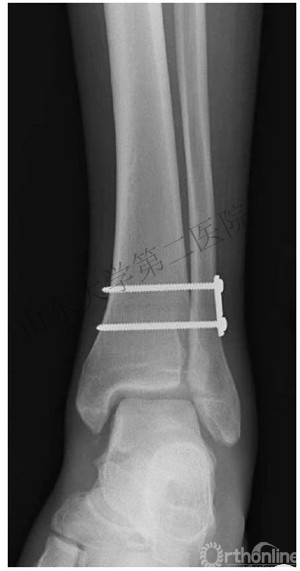

(2)下胫腓联合以两枚下胫腓螺钉固定。

*胫距关节面近端2-4cm,并且平行于关节面。

*水平面上从后向前有30°夹角。

*2枚螺钉or1枚?

有高位腓骨骨折时,打2枚螺钉;其他的打1枚螺钉。

4.下胫腓联合需要用两枚下胫腓螺钉固定,除非可以确定下胫腓联合是否稳定。

5.在固定下胫腓联合的时候,需要恢复腓骨长度和旋转,将足放于中立位。